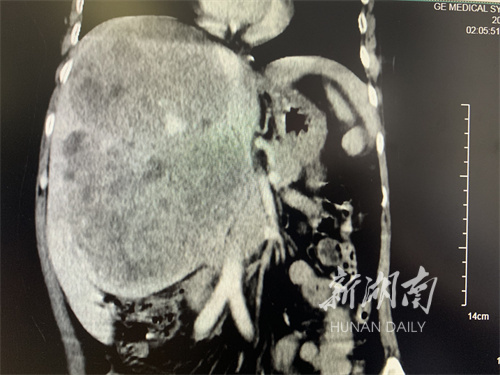

去年9月,53岁的刘某因为腹部隆起、隐痛,在当地医院查出右肝多发巨大团块状占位,医生建议去上级医院求医。

1月14日下午,罗宏武、张玉平带领手术团队为患者进行切除手术。由于瘤体长时间地挤压,肝动脉、门静脉及胆管完全失去了正常的解剖结构,且巨大的瘤体严重限制术者的视野和操作空间。手术团队凭借精湛技能和丰富经验,经5个小时,最终成功沿着中肝静脉、下腔静脉和瘤体边缘仅5mm的缝隙,将瘤体侵犯的右半肝及尾状叶完整切除。取出的标本体积为24x18x16cm,重量为2.35kg,为两个巨大瘤体的融合灶。

罗宏武介绍,很多肝脏恶性肿瘤一经发现往往已是中晚期,多不具备手术条件。该例患者肿瘤达24cm,临床很少见,但无卫星转移结节,无血管癌栓,手术有望获得良好效果。“近年肝癌治疗有很大进展,新兴的转化治疗给既往认为不具备手术条件的肝癌患者争取了手术机会,降低了复发风险。”罗宏武说。